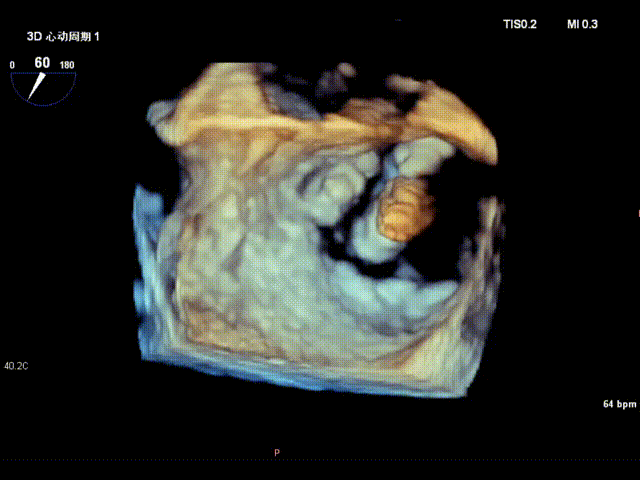

术前食道超声示: 二尖瓣重度反流,1区脱垂并累及外交界。

术前食道超声-3D

术前食道超声3D血流